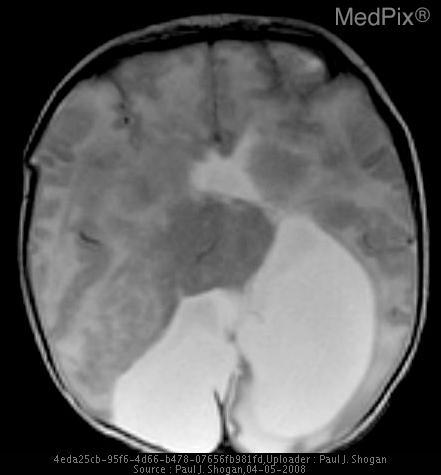

The MedPix-VQA dataset is a comprehensive medical Visual Question-Answering dataset designed for training and evaluating VQA models in the medical domain. It contains medical images from MedPix, a well-known medical image database, paired with questions and answers that focus on medical image interpretation.

Given the following image:

Sample image from the MedPix dataset

And the prompt:

How does the interhemispheric fissure appear in this image?

Example Gemma 3 response:

The interhemispheric fissure appears as a dark streak, indicating significant tissue loss.

Example Gemma 3n response:

The interhemispheric fissure appears somewhat obscured by the fluid-filled mass.